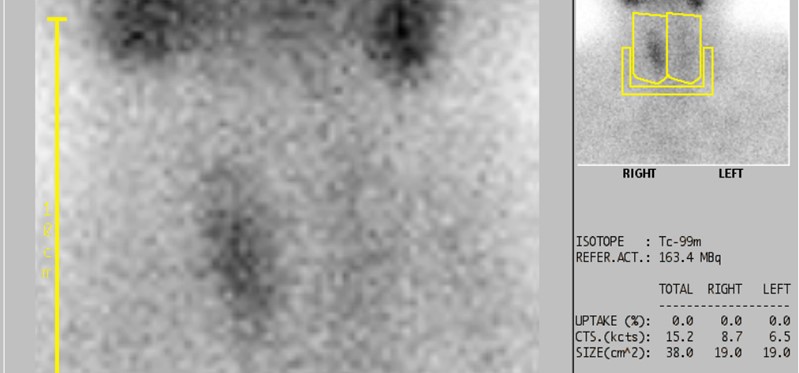

Scintigraphy